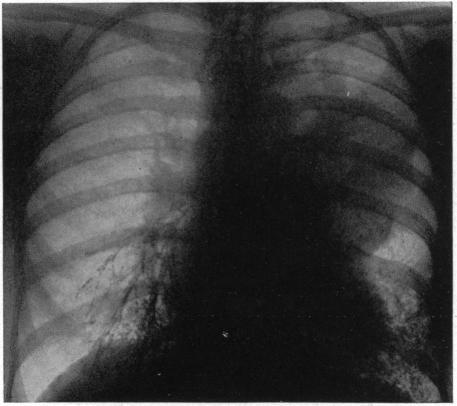

INTRATHORACIC DERMOIDS: WITH THE REPORT OF A CASE OF TOTAL EXTIRPATION AT ONE SITTING BY A NEW METHOD OF THORACOTOMY.

Ann Surg. 1928 Sep;88(3):607-32. doi: 10.1097/00000658-192809000-00030.